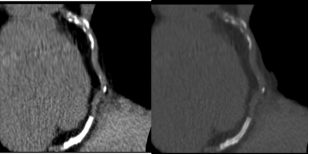

冠状动脉血管CT成像(CTA)

冠状动脉血管CT成像是一种非侵入性检查方法,它通过向血管内注入对比剂,再利用CT扫描清晰显示冠状动脉的解剖结构。此方法的原理类似于我们打开水管并注入染色剂来观察水管内部的情况。当对比剂与血液流入冠状动脉时,它会增强血液的信号,使得血管壁、血液流动、以及钙化斑块等成分的信号有所不同,从而使医生能够清晰地观察到冠状动脉的病变情况。通过三维重建技术,CTA能够多角度地呈现冠状动脉的形态,准确判断血管是否狭窄、狭窄的程度以及是否存在钙化斑块。研究表明,CTA的灵敏度和特异性较高,特别是在判断冠状动脉狭窄和钙化斑块时,准确性较好。

然而,CTA也并非没有缺点。首先,CTA需要向患者注射对比剂,对于那些存在肾功能不全、过敏反应或对比剂过敏史的患者,这种检查方法就不适用了。此外,CTA检查还要求患者在检查过程中进行良好的配合,尤其是憋气。如果患者未能按照要求完成配合,检查结果可能会受到影响。尽管如此,CTA依然是一种高效且可靠的检查工具,尤其适用于需要进一步评估冠状动脉情况的高风险患者。